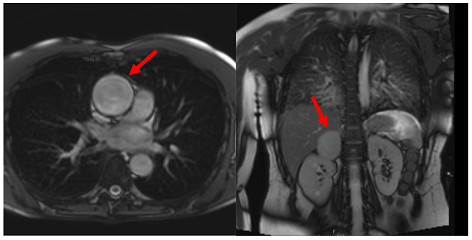

5. Cardiovascular Magnetic Resonance

Hypertensive patients with LV hypertrophy disproportionate to the degree of hypertension may be referred for CMR for further examination and differential diagnosis. CMR is regarded as the non-invasive gold standard for the evaluation of LV volumes, systolic function, LV mass, and myocardial tissue characterisation [26]. Image acquisition can be achieved largely independent of body habitus, imaging windows, and without ionising radiation exposure [26]. Cardiac images are usually acquired in four-, three-, and two-chamber views, as well as a full stack of 10–15 short-axis images. Its three-dimensional nature with excellent spatial resolution and high tissue contrast enables accurate measurement of cardiac function and morphology: LV volumes, mass, and the ejection fraction, as well as an assessment of regional wall motion abnormalities without relying on geometrical assumptions (such as Simpson’s biplane method) [27]. CMR provides the potential to also assess and quantify focal and diffuse myocardial fibrosis caused by hypertension (hypertension-mediated organ damage) and to screen for secondary causes of hypertension [28]. The nascent technique of cardiac MR elastography can also allow the non-invasive measurement of myocardial stiffness [29]. Importantly, the high accuracy and precision of CMR allow prognostically important longitudinal changes in LV mass in response to therapy to be readily appreciated [30]

Table 3 summarises a suggested CMR scan protocol for the diagnosis of presumed HHD and differential diagnosis of patients with a “thickened left ventricle”.

Table 3.

The cardiovascular magnetic resonance protocol used for assessment of hypertensive patients. The described protocol can be acquired within 45–50 min. Images are examples from patients with hypertensive heart disease.

Similar to echocardiography, LV geometry can be assessed using relative wall thickness (RWT) and CMR-specific normal values for LV myocardial mass (Figure 2). LA dimensions can be assessed with Simpson’s biplane or area-length methods from the standard views, or more precisely with a volumetric assessment using an atrial short-axis stack. LA enlargement is a reliable marker of diastolic dysfunction (chronically elevated LV filling pressures) in the absence of mitral valve disease [31]. The recently introduced left atrial coupling index (LACI) is a ratio of the indexed left atrial end-diastolic volume (LAVI) in relation to the left ventricular end-diastolic volume (LVEDVI) [32]. This ratio may offer prognostic information regarding cardiovascular events such as atrial fibrillation, heart failure, and coronary artery disease-related death.

Figure 2.

Tissue characterization with Late Gadolinium Enhancement (LGE) and Extracellular Volume (ECV) Map. Adapted with permission from [33].

To avoid the low but important risks of endomyocardial biopsy, which can have an overall complication rate of up to 6% [2], myocardial fibrosis can be assessed non-invasively using CMR: LGE is suitable for detecting irreversible replacement fibrosis and myocardial scarring and T1/ECV mapping for detection of potentially reversible (reactive) interstitial and more diffuse fibrosis (not detectable by LGE) (Figure 2).